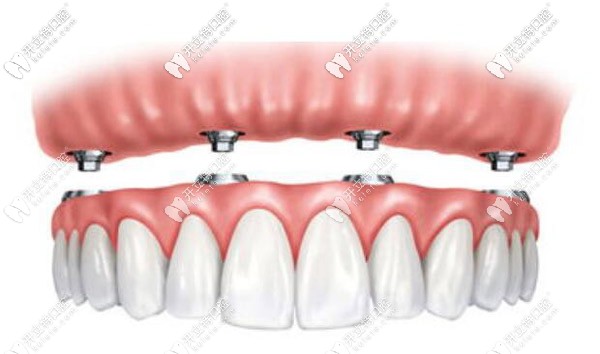

半固定和全固定還是有區(qū)別的:

半固定種植圖示

半固定就是可以還是可以摘卸的,半固定式的是需要三餐后取下來清潔的,全固定就像自己的牙齒一樣,只需要飯后刷牙進(jìn)行清潔就好。